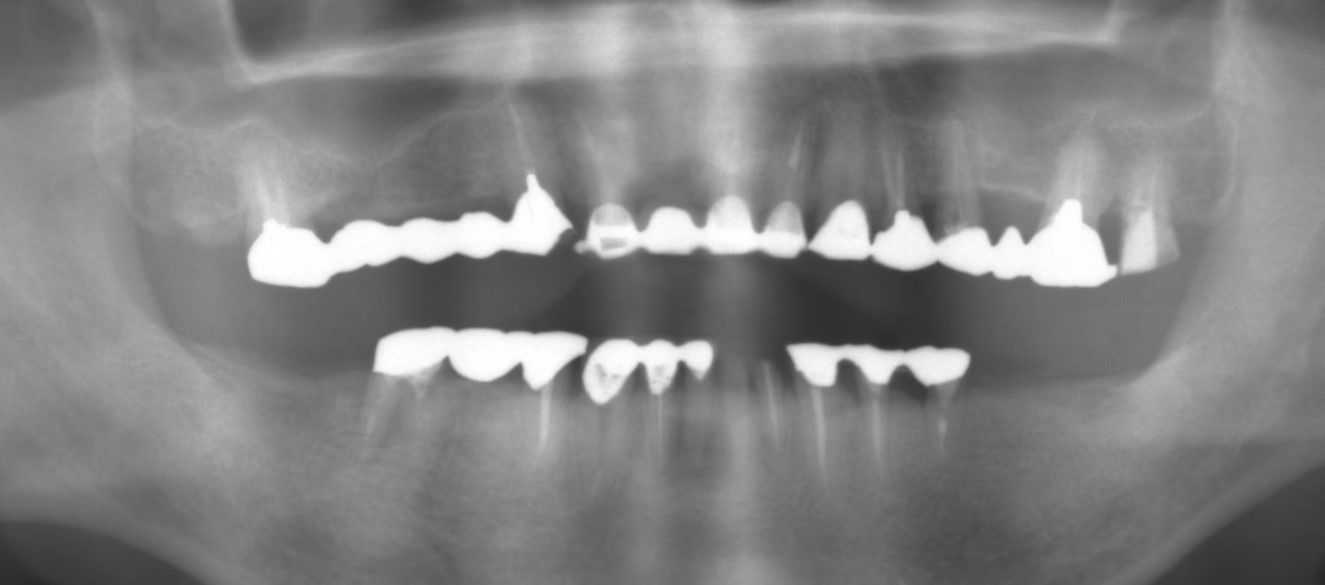

術前レントゲン

術後レントゲン

術後レントゲン

| 主訴 | 奥歯が咬めなくて前歯が出てきた。 奥歯を治療したあと、咬み合わせがもし落ち着いたら前歯も治療したい。 |

|---|---|

| 年代・性別 | 30代 女性 |

| 治療部位 | 下顎両側 67 |

| 治療費用 | インプラント 420,000円×4本 静脈内鎮静法 75,000円×2回 |

| 治療期間 |

10ヶ月 |